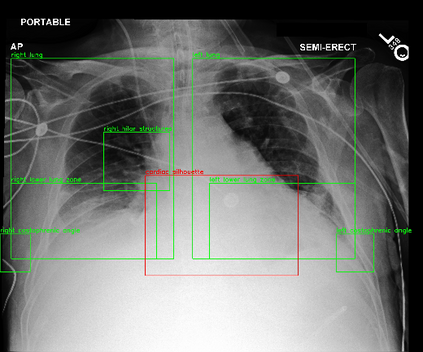

Despite the progress in utilizing deep learning to automate chest radiograph interpretation and disease diagnosis tasks, change between sequential Chest X-rays (CXRs) has received limited attention. Monitoring the progression of pathologies that are visualized through chest imaging poses several challenges in anatomical motion estimation and image registration, i.e., spatially aligning the two images and modeling temporal dynamics in change detection. In this work, we propose CheXRelNet, a neural model that can track longitudinal pathology change relations between two CXRs. CheXRelNet incorporates local and global visual features, utilizes inter-image and intra-image anatomical information, and learns dependencies between anatomical region attributes, to accurately predict disease change for a pair of CXRs. Experimental results on the Chest ImaGenome dataset show increased downstream performance compared to baselines. Code is available at https://github.com/PLAN-Lab/ChexRelNet

翻译:尽管在利用深层学习实现胸前射线解释和疾病诊断任务自动化方面取得了进展,但连续的胸前X射线(CXRs)之间的变化受到的注意有限。通过胸前成像可视化的病理进展监测在解剖运动估计和图像登记方面带来了若干挑战,即在空间上对两种图像进行匹配,在变化检测中模拟时间动态。在这项工作中,我们提议CheXRelNet,这是一个神经模型,可以跟踪两个CXRs之间的纵向病理变化关系。CheXRelNet包含当地和全球的视觉特征,利用图像间和图像内解剖学信息,并学习解剖区域属性之间的依赖性,准确预测两对CXR的疾病变化。Chest ImaGenome数据的实验结果显示,与基线相比,下游的性能有所增加。代码可在https://github.com/PLAN-Lab/CexRelNet上查阅。